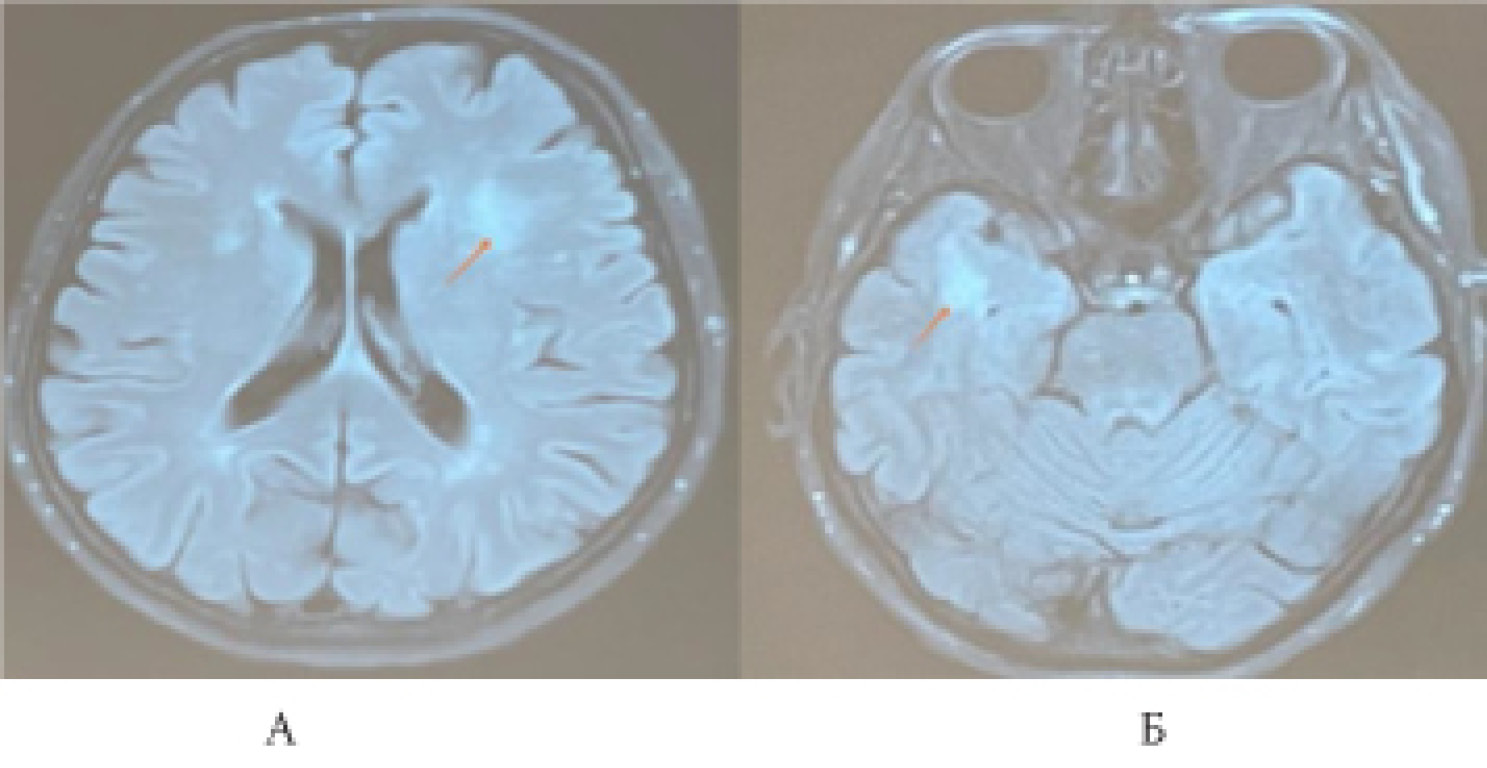

МРТ головного мозга с внутривенным контрастированием от 23.03.2021. Субкортикально и паравентрикулярно в белом веществе головного мозга в височных, лобных и теменных долях (от 4 до 8 мм), в левой лобной доле (16×14 мм), в правой височной доле (до 20×13 мм), в области базальных ядер (до 3 мм) визуализируются множественные очаги глиоза с нечёткими контурами, склонные к слиянию, характеризующиеся гиперинтенсивным сигналом на Т2-взвешенных изображениях (ВИ), изоинтенсивным на Т1-ВИ, без перифокального отёка и масс-эффекта. Очаги не имеют признаков ограничения и магнитно-резонансной (МР) диффузии, не накапливают контрастное вещество (рис. 2).

Рис. 2. Очаги гиперинтенсивного магнитно-резоненсного сигнала на Т2-взвешенном изображении и импульсная последовательность FLAIR в правой височной доле (Б); в белом веществе лобных долей

Заключение. МР-картина множественных очаговых изменений головного мозга дистрофического и дисциркуляторного характера, без признаков ограничения МР-диффузии и накопления контрастного вещества. Умеренная наружная заместительная гидроцефалия. Учитывая относительно молодой возраст пациентки и выраженные изменения белого вещества головного мозга, помимо ранних морфологических проявлений дисциркуляторной энцефалопатии, необходимо исключить наличие генетически детерминированной артериолопатии по типу ЦАДАСИЛ (поражение височных долей, ранний клинический признак — мигрень, снижение памяти). Демиелинизирующий процесс вне стадии активности — наименее вероятен (очаги в области мозолистого тела отсутствуют).